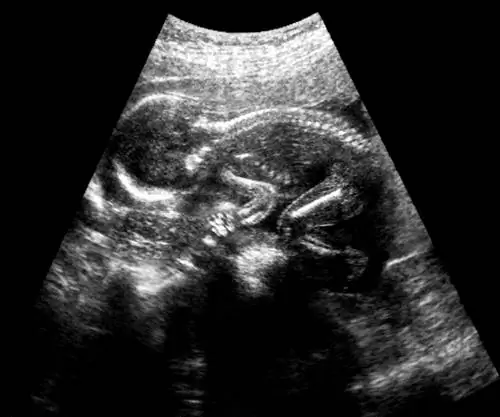

Ультразвуковое изображение плода в утробе матери.